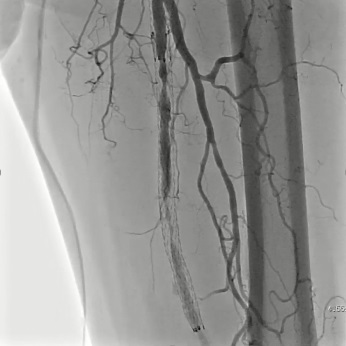

Режим Dynamic trace

Dynamic trace – режим дослідження кінцівок, передбачає рух деки столу за напрямком поширення контрастної речовини по периферичних судинах в режимі рентгенографії.